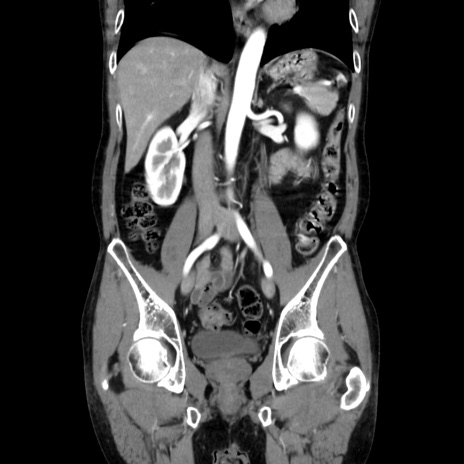

症例37(冠状断像)

【症例】40歳代 男性

【主訴】腹痛

【現病歴】4時間ほど前に電車に乗車中に臍部上より腹痛出現。徐々に増悪し起立困難となり、救急外来受診。生ものは数日食べていない。今朝お雑煮を食べた。

【身体所見】BT 36.8℃、BP 117/84mmHg、HR 91/min、SpO2 97%、苦悶様、腹部:臍上部広範囲圧痛あり、反跳痛±

【データ】WBC 8100、CRP 0.03